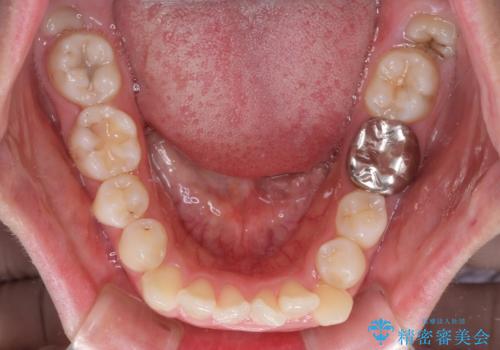

口ゴボが気になる 上下4本の抜歯矯正

- 前歯のデコボコやクロスバイト、口元の突出感を気にして来院された患者様です。

上下左右の第一小臼歯4本を抜歯して、ワイヤー装置にて矯正治療を行うこととしました。

途中出産や育児があり、治療期間長くなってしまいましたが、ストレスなく唇が閉じられるような口元に仕上げることができました。